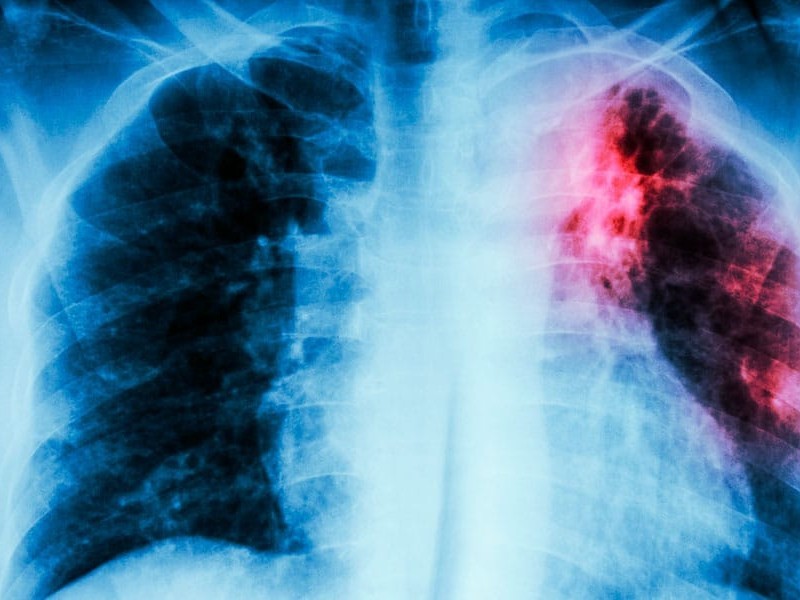

El estado de Sonora registra 1322 casos de tuberculosis en éste 2025, de acuerdo a datos del Sistema Único de Información para la Vigilancia Epidemiológica, que pertenece a la secretaria de Salud en la entidad

Aunque no se especificó una lista de entidades con sus números de casos, en la Semana epidemiológica 29, se indicó que el Estado de Sonora se posiciona en el segundo sitio a nivel nacional con una tasa alta de la enfermedad por habitantes

La tuberculosis, es una enfermedad que se transmite al momento que una persona con éste padecimiento emite un estornudo o tose, las partículas permanecen en el aire y se conservan activas durante 15 minutos en lugares reducidos o cerrados